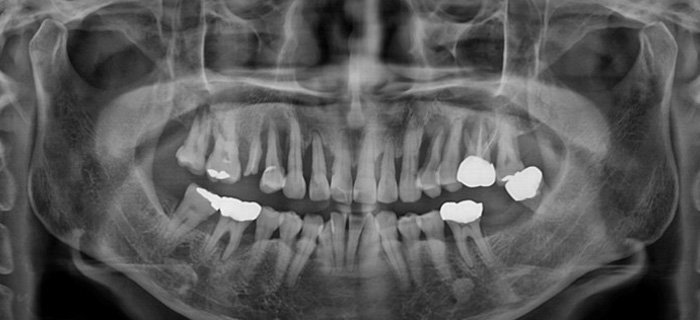

- 안심플란트의 임플란트는 자연치아를 최대한 보존함과 동시에 치아 상실로 인한 불편감과

- 이 때문에 발생하는 턱관절장애, 치주병 등을 사전에 방지합니다.

치아가 빠졌거나

어금니가 없으신 분